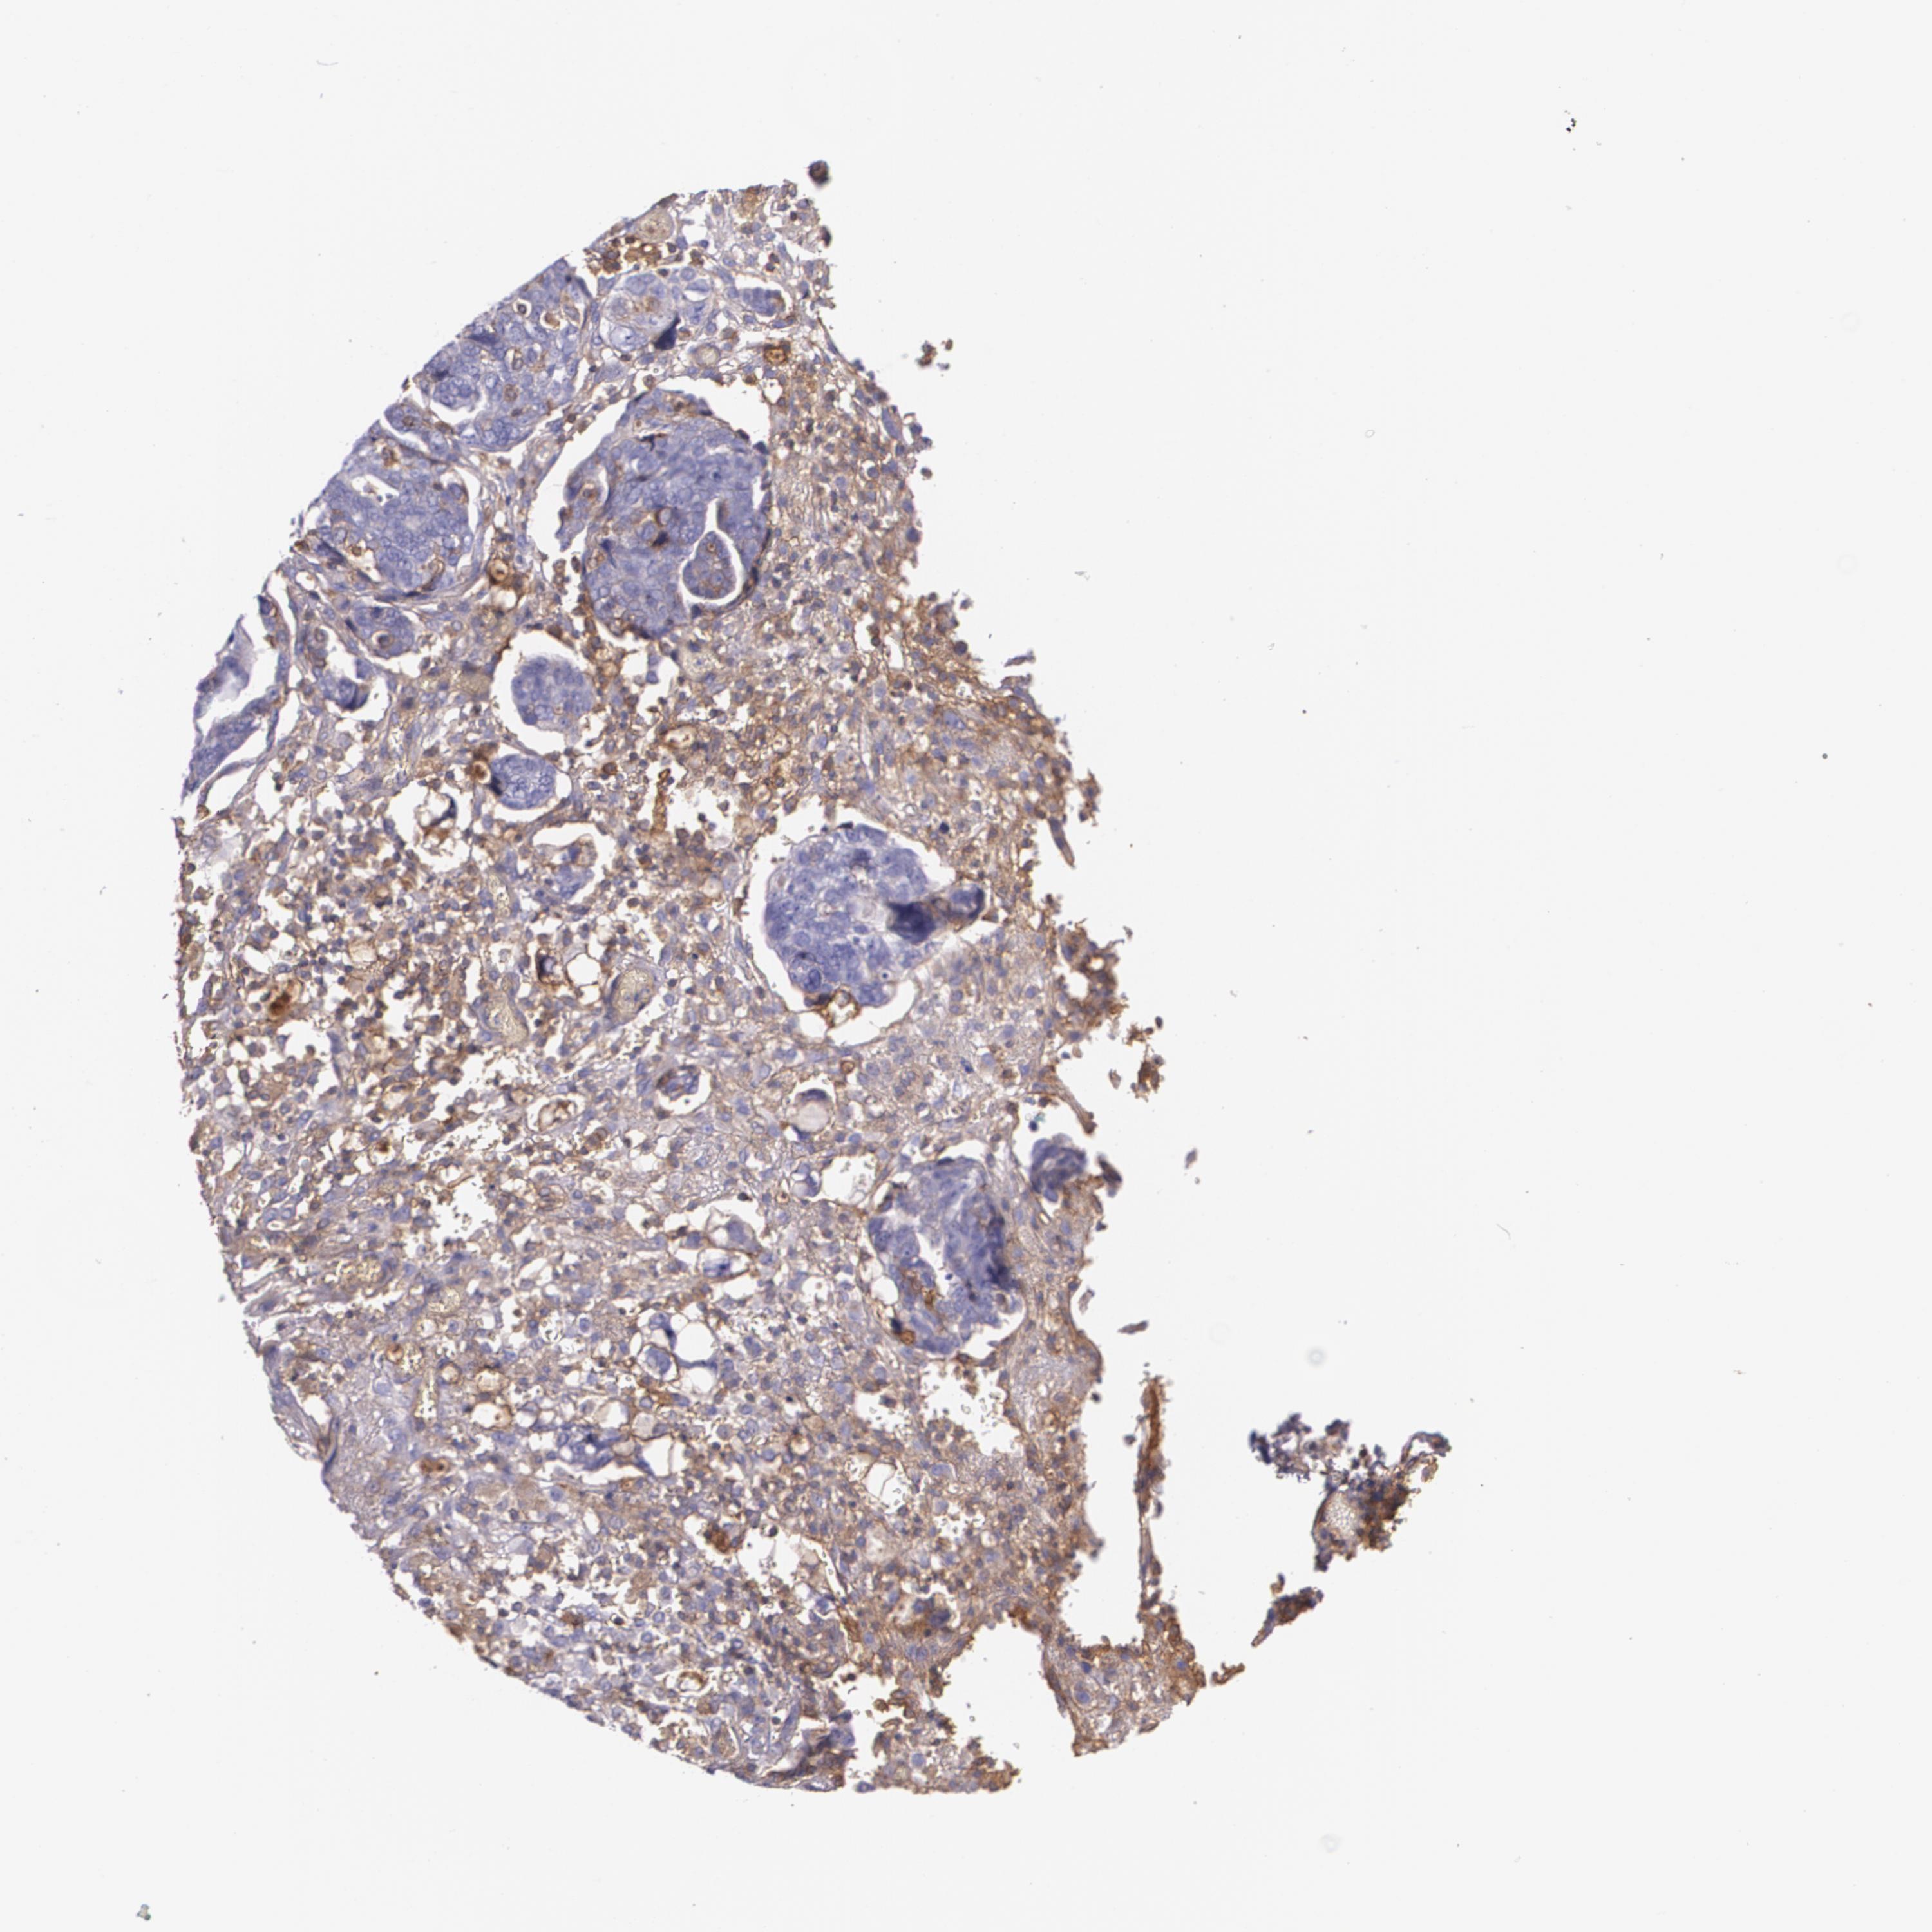

OVARIAN CANCER - Protein expressioni

A mouse-over function shows sample information and annotation data. Click on an image to view it in a full screen mode. Samples can be filtered based on level of antibody staining by selecting one or several of the following categories: high, medium, low and not detected. The assay and annotation is described here.

Note that samples used for immunohistochemistry by the Human Protein Atlas do not correspond to samples in the TCGA dataset.

Antibody stainingi

Antibody staining in the annotated cell types in the current human tissue is reported as not detected, low, medium, or high, based on conventional immunohistochemistry profiling in selected tissues. This score is based on the combination of the staining intensity and fraction of stained cells.

Each image is clickable and will lead to virtual microscopy that enables deeper exploration of all samples and also displays staining intensity scores, fraction scores and subcellular localization as well as patient and tissue information for each sample.

Antibody CAB002572

Cystadenocarcinoma, serous, NOS

Carcinoma, endometroid

Carcinoma, NOS

Cystadenocarcinoma, mucinous, NOS